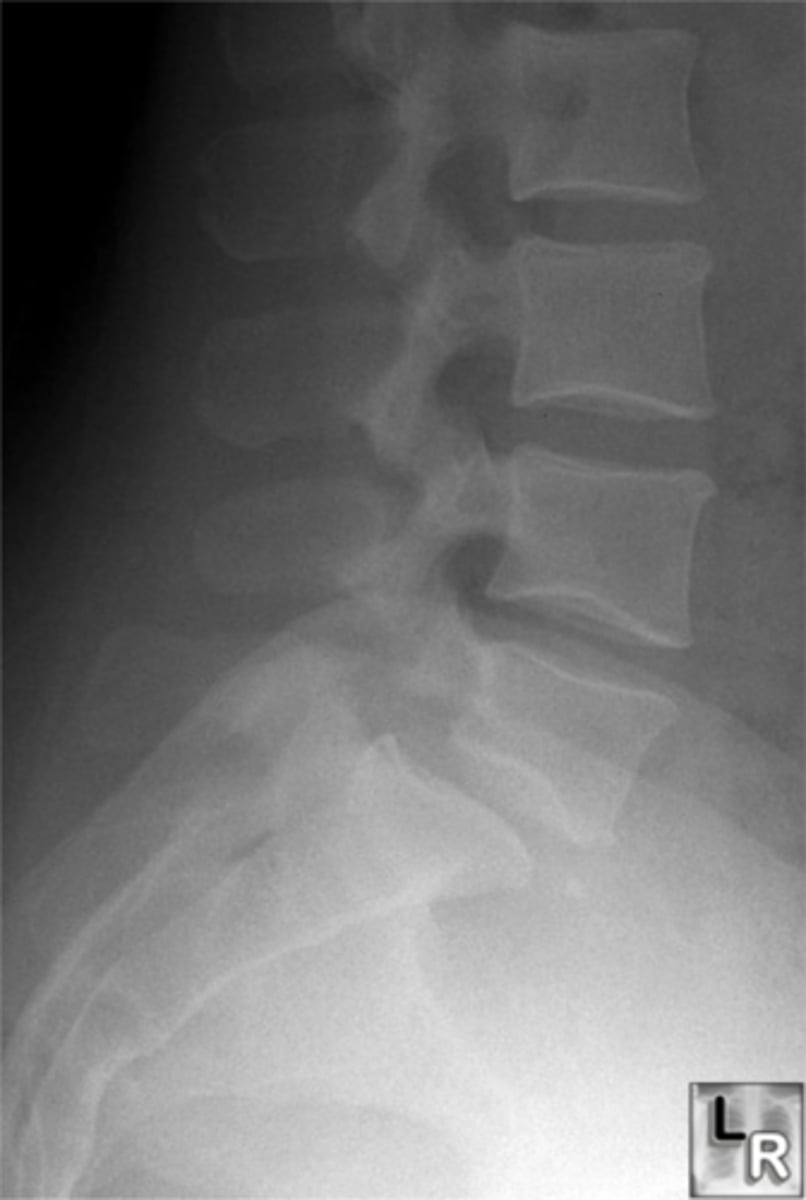

Vignette #1:

Sex: Male

Age: 62

Chief Complaint: Patient presents with low back pain and initiating urinary streams. He reports polyuria in the middle of the night.

Objective Findings: Kemps + Diagnostic Imaging: X-ray